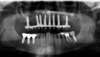

AVANT : la maladie parodontale a entraîné la perte de toutes les dents maxillaires

APRES : la greffe des deux sinus maxillaires a permis au patient de bénéficier d’une solution FIXE sur 8 implants.